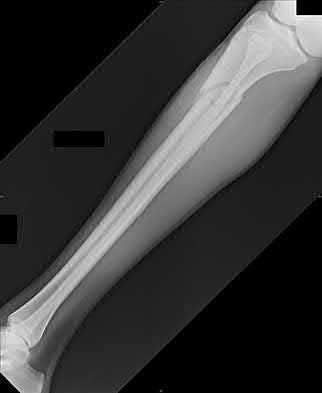

2. # A 35-year-old woman is involved in a head-on collision while driving. Initial radiographs are shown in Figures 8a and 8b. Injury to what vessel increases the risk for osteonecrosis of the injured bone?

5. Artery of the tarsal sinus Corrent answer: 4

The patient has a Hawkins type III talar neck fracture-dislocation with a risk of osteonecrosis ranging from 69% to 100%. Anatomic studies have shown that the artery of the tarsal canal supplies the lateral two thirds of the talar body.

The other vessels listed provide no significant contribution to the talus.